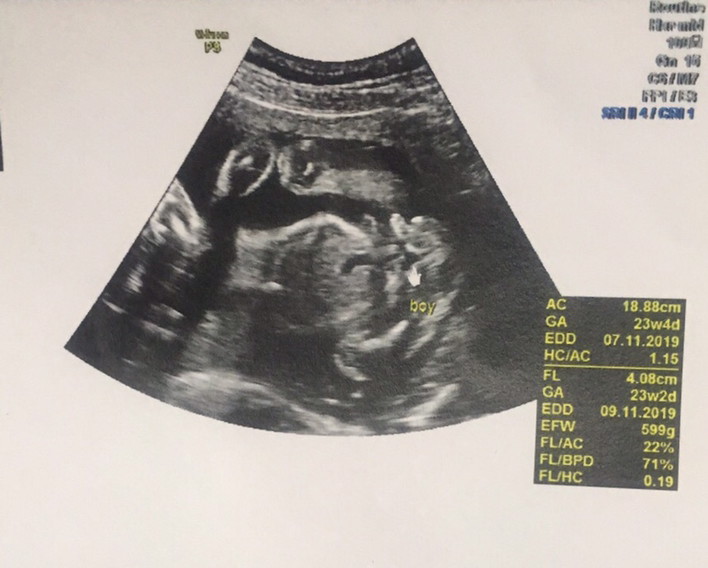

เห็นค่ะ ซาวน์ตอน23week